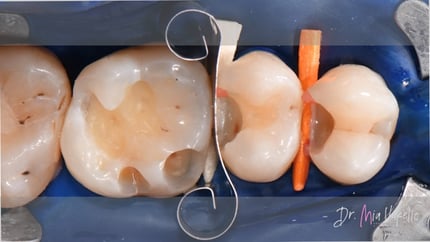

Tras realizar un aislamiento adecuado con dique de goma y colocar las cuñas, se inició la preparación cavitaria con una fresa cilíndrica. Después de retirar la restauración, se procedió a eliminar la dentina desmineralizada con una fresa de acero. El refinamiento final de la cavidad consistió en transformar las paredes convergentes en divergentes y pulir la superficie interna de la cavidad con fresas de diamante para pulido.

Para la restauración de la pared proximal, se utilizaron las matrices Halo™ y el anillo Halo™ de Ultradent Products.

Se empleó la técnica centrípeta modificada. El paso inicial consistió en aplicar una capa de resina fluida de 0.5 mm de espesor (Tetric EvoFlow™, Ivoclar*).

El material utilizado para la restauración fue la resina Transcend™ (Ultradent Products). La pared proximal se realizó con el tono EW, mientras que las dos capas horizontales posteriores se colocaron en tono A3D. Las características secundarias se lograron utilizando el modificador de color Kolor + Plus™ en tono café (Kerr*).